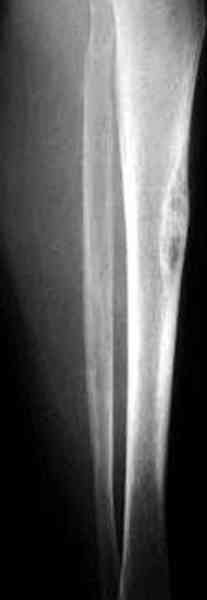

"При его рассмотрении с рентгенологом и морфологом сошлись, что это не фиброзная дисплазия, что было первым предположением по рентгенограммам. В полости было и мягкотканое образование. Окончательно заключение дадут через несколько дней"

По локализации и по характреру опухоли мало напоминает остеобластому, может, представленные биопсийные материалы адамантиномы помогут вашим морфологам дифференцировать опухоль (Basiloid cells, pseudoglandular pattern and peripheral palisading)

Недавно на нашей ежемесячной Morbidity&Mortality

conference мы разбирали похожий случай, ложный сустав большеберцовой кости после резекции опухоли.

К нашему онкологу-ортопеду обратился больной с жалобами на боли в голени, из рассказа - год назад была сделана биопсия большеберцовой кости, но название заболевания "не запомнил”.

В литературе "A Classic Adamantinoma Arising from

Osteofibrous Displasialike Adamantinoma in the Lower Leg: A case report and Review of the Literature похожие снимки.

Наши имели проблему со сращением, пришлось им сделать динамизацию, дополнительную аутопластику.

Снимки представлены.